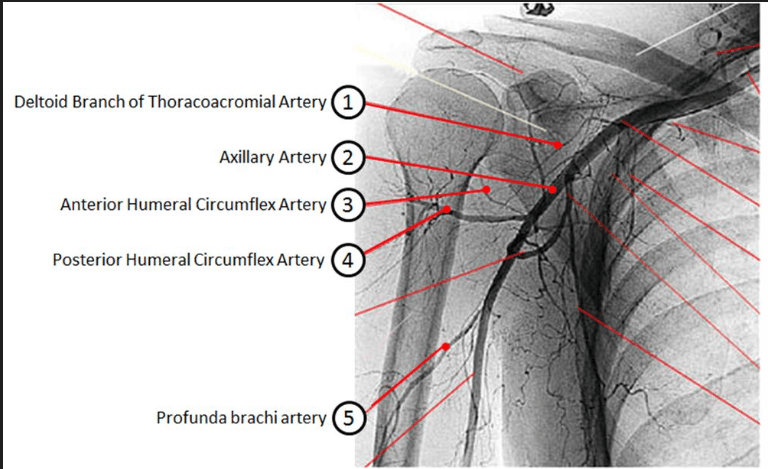

A 67-year-old female who sustained a proximal humerus fracture as a result of a fall goes on to develop avascular necrosis (AVN). An injury was most likely sustained to which of the following arteries labeled 1-5 in Figure A?

Posterior circumflex artery

During placement of a locking proximal humerus plate, one must place the plate lateral to the bicipital groove and pectoralis major tendon to avoid injury to this structure

anterior humeral circumflex artery